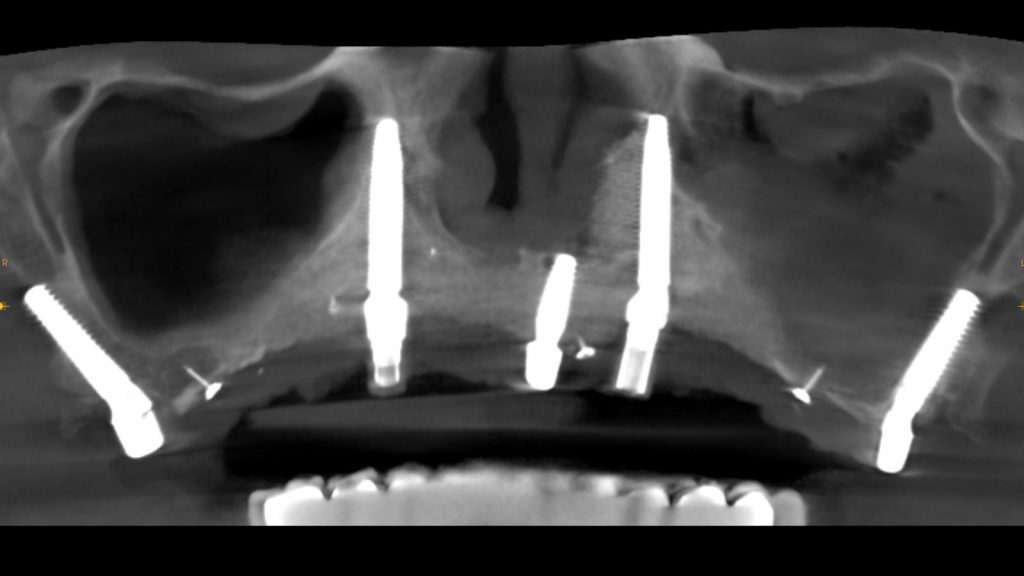

IMPLANTES TRANSNASALES Y CIGOMÁTICOS

El caso que os presentamos en este artículo se corresponde al de una paciente de 67 años que, tras varios intentos fallidos de rehabilitación oral mediante distintas técnicas, acude a nuestra clínica dental en Valencia buscando un tratamiento de implantes viable.

Si bien es cierto que la evolución en diseño y materiales de los implantes dentales nos permite realizar intervenciones más complejas de un modo menos invasivo, en ocasiones, la falta de hueso nos obliga a practicar técnicas de regeneración ósea.

Sin embargo, estas técnicas suelen ser más largas e invasivas, ya que requieren varias intervenciones. Cuando la colocación de implantes necesita un injerto óseo previo, primero se realiza la cirugía del injerto y, tras varios meses de consolidación, una segunda intervención para colocar los implantes.